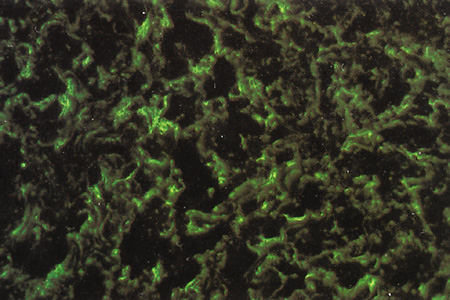

Fig. 2. Immunofluorescence microscopy (100×) using antihyaluronic acid antibodies. Fetal sclera, week 19 of development (A) and adult sclera (B). The moderate amount of hyaluronic acid seen in the 19-week fetal specimen steadily decreases through posterior gestational periods and is nearly absent in adult sclera.